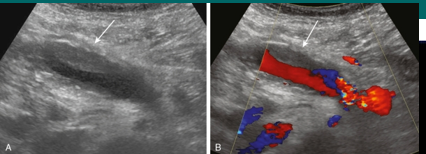

HA thrombosis

HAT